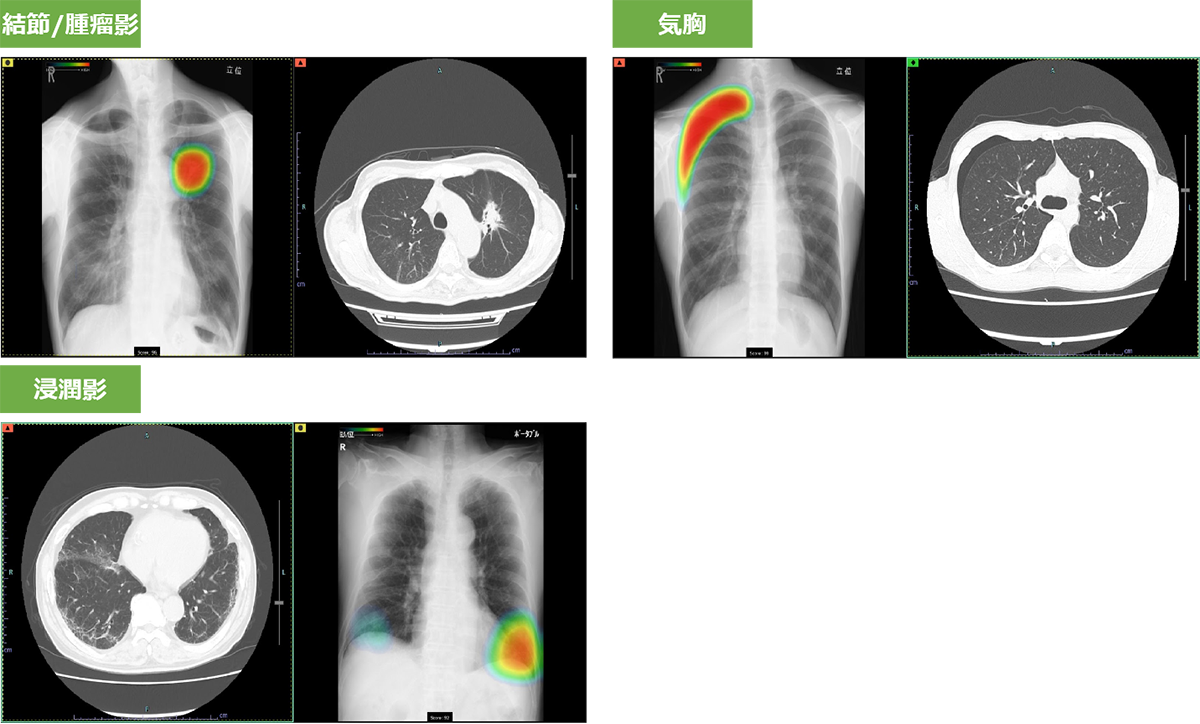

胸部レントゲン検査